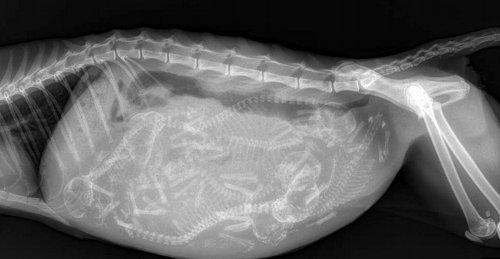

И ответ на популярный вопрос: "может ли у выводка котят быть не один отец? - да, такое возможно, и называется это явление суперфекундацией. Когда у кошки наступает период половой активности, на ее мяуканье и характерный запах сбегаются коты со всей округи. Некоторые кошки разрабатывают специальную стратегию привлечения одного конкретного кота и отвергают других ухажеров в ожидании фаворита.

Но чаще всего с ней всё-таки спариваются несколько котов. Это означает, что ее оплодотворяет "Коктейль" из спермы разных самцов и выяснить отцовство не представляется возможным. Результатом становится выводок самых разнообразных котят.